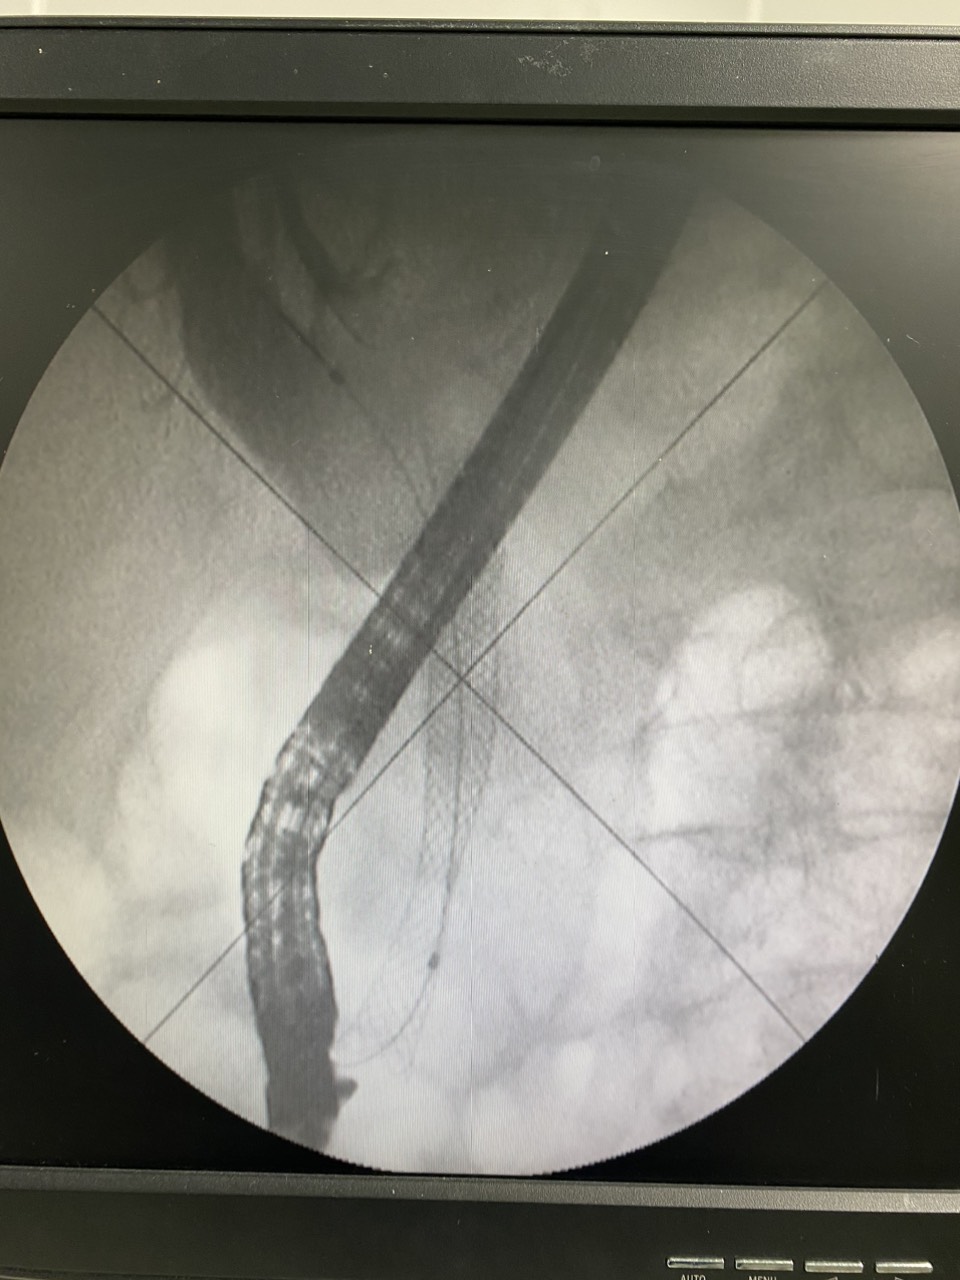

Hình ảnh chụp dưới Carm stent sau khi đặt vào đường mật.

Chiều 11/6, bệnh nhân được Ekip Khoa Nội tiêu hóa thực hiện phương pháp nội soi Ercp đặt stent metallic, kỹ thuật này cũng được thực hiện như một ca Ercp thông thường và được thực hiện thường quy tại Bệnh viện Đa khoa Trung ương Quảng Nam. Tiến trình nội soi, bác sĩ sẽ đưa 1 ống soi cửa sổ bên vào đến nhú vater sau đó đưa dụng cụ ngược dòng vào đường mật để tiến hành can thiệp stent.